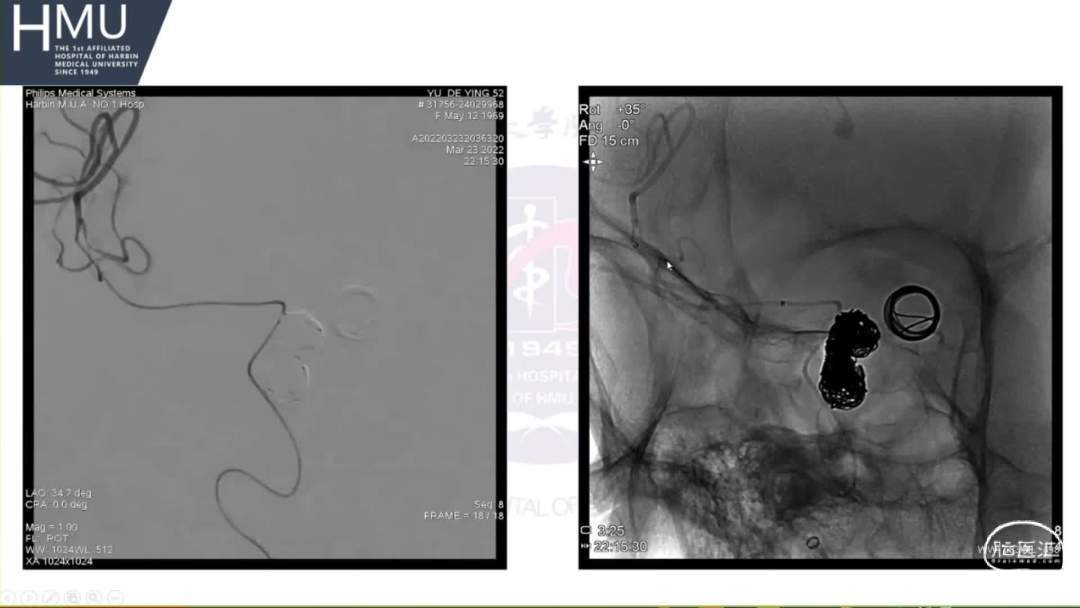

21:00覆膜支架置入术

海绵窦段动脉瘤如何导致蛛网膜下腔出血?

破裂致下腔出血可能因素

●大动脉瘤累及突破海绵窦硬膜